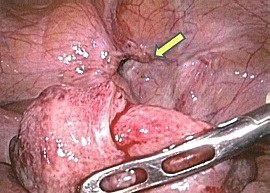

手術画像